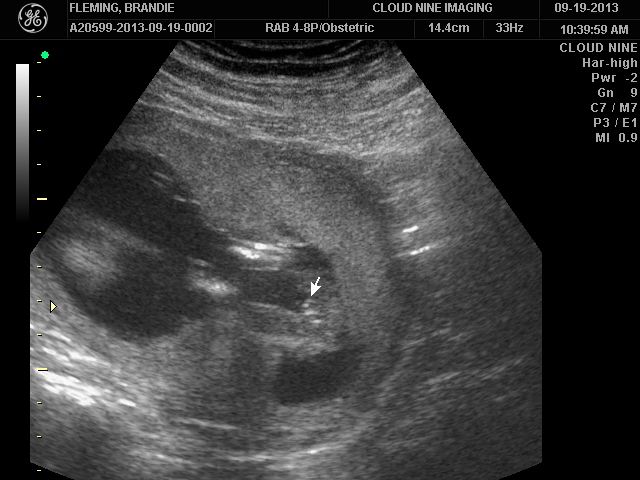

I went to a private u/s clinic at a little over 17 weeks and she firmly told me "it's a girl", however after two boys I can't seem to let it digest and I need a little reassurance. I don't go back for my 20 wk u/s at my doctors office until the second week in Oct and I'm a nervous wreck. I want to call this baby a "her" and of course call her by her sweet name that we have chosen. So please help ease my mind! Thank you so much!!

Attachment 14418